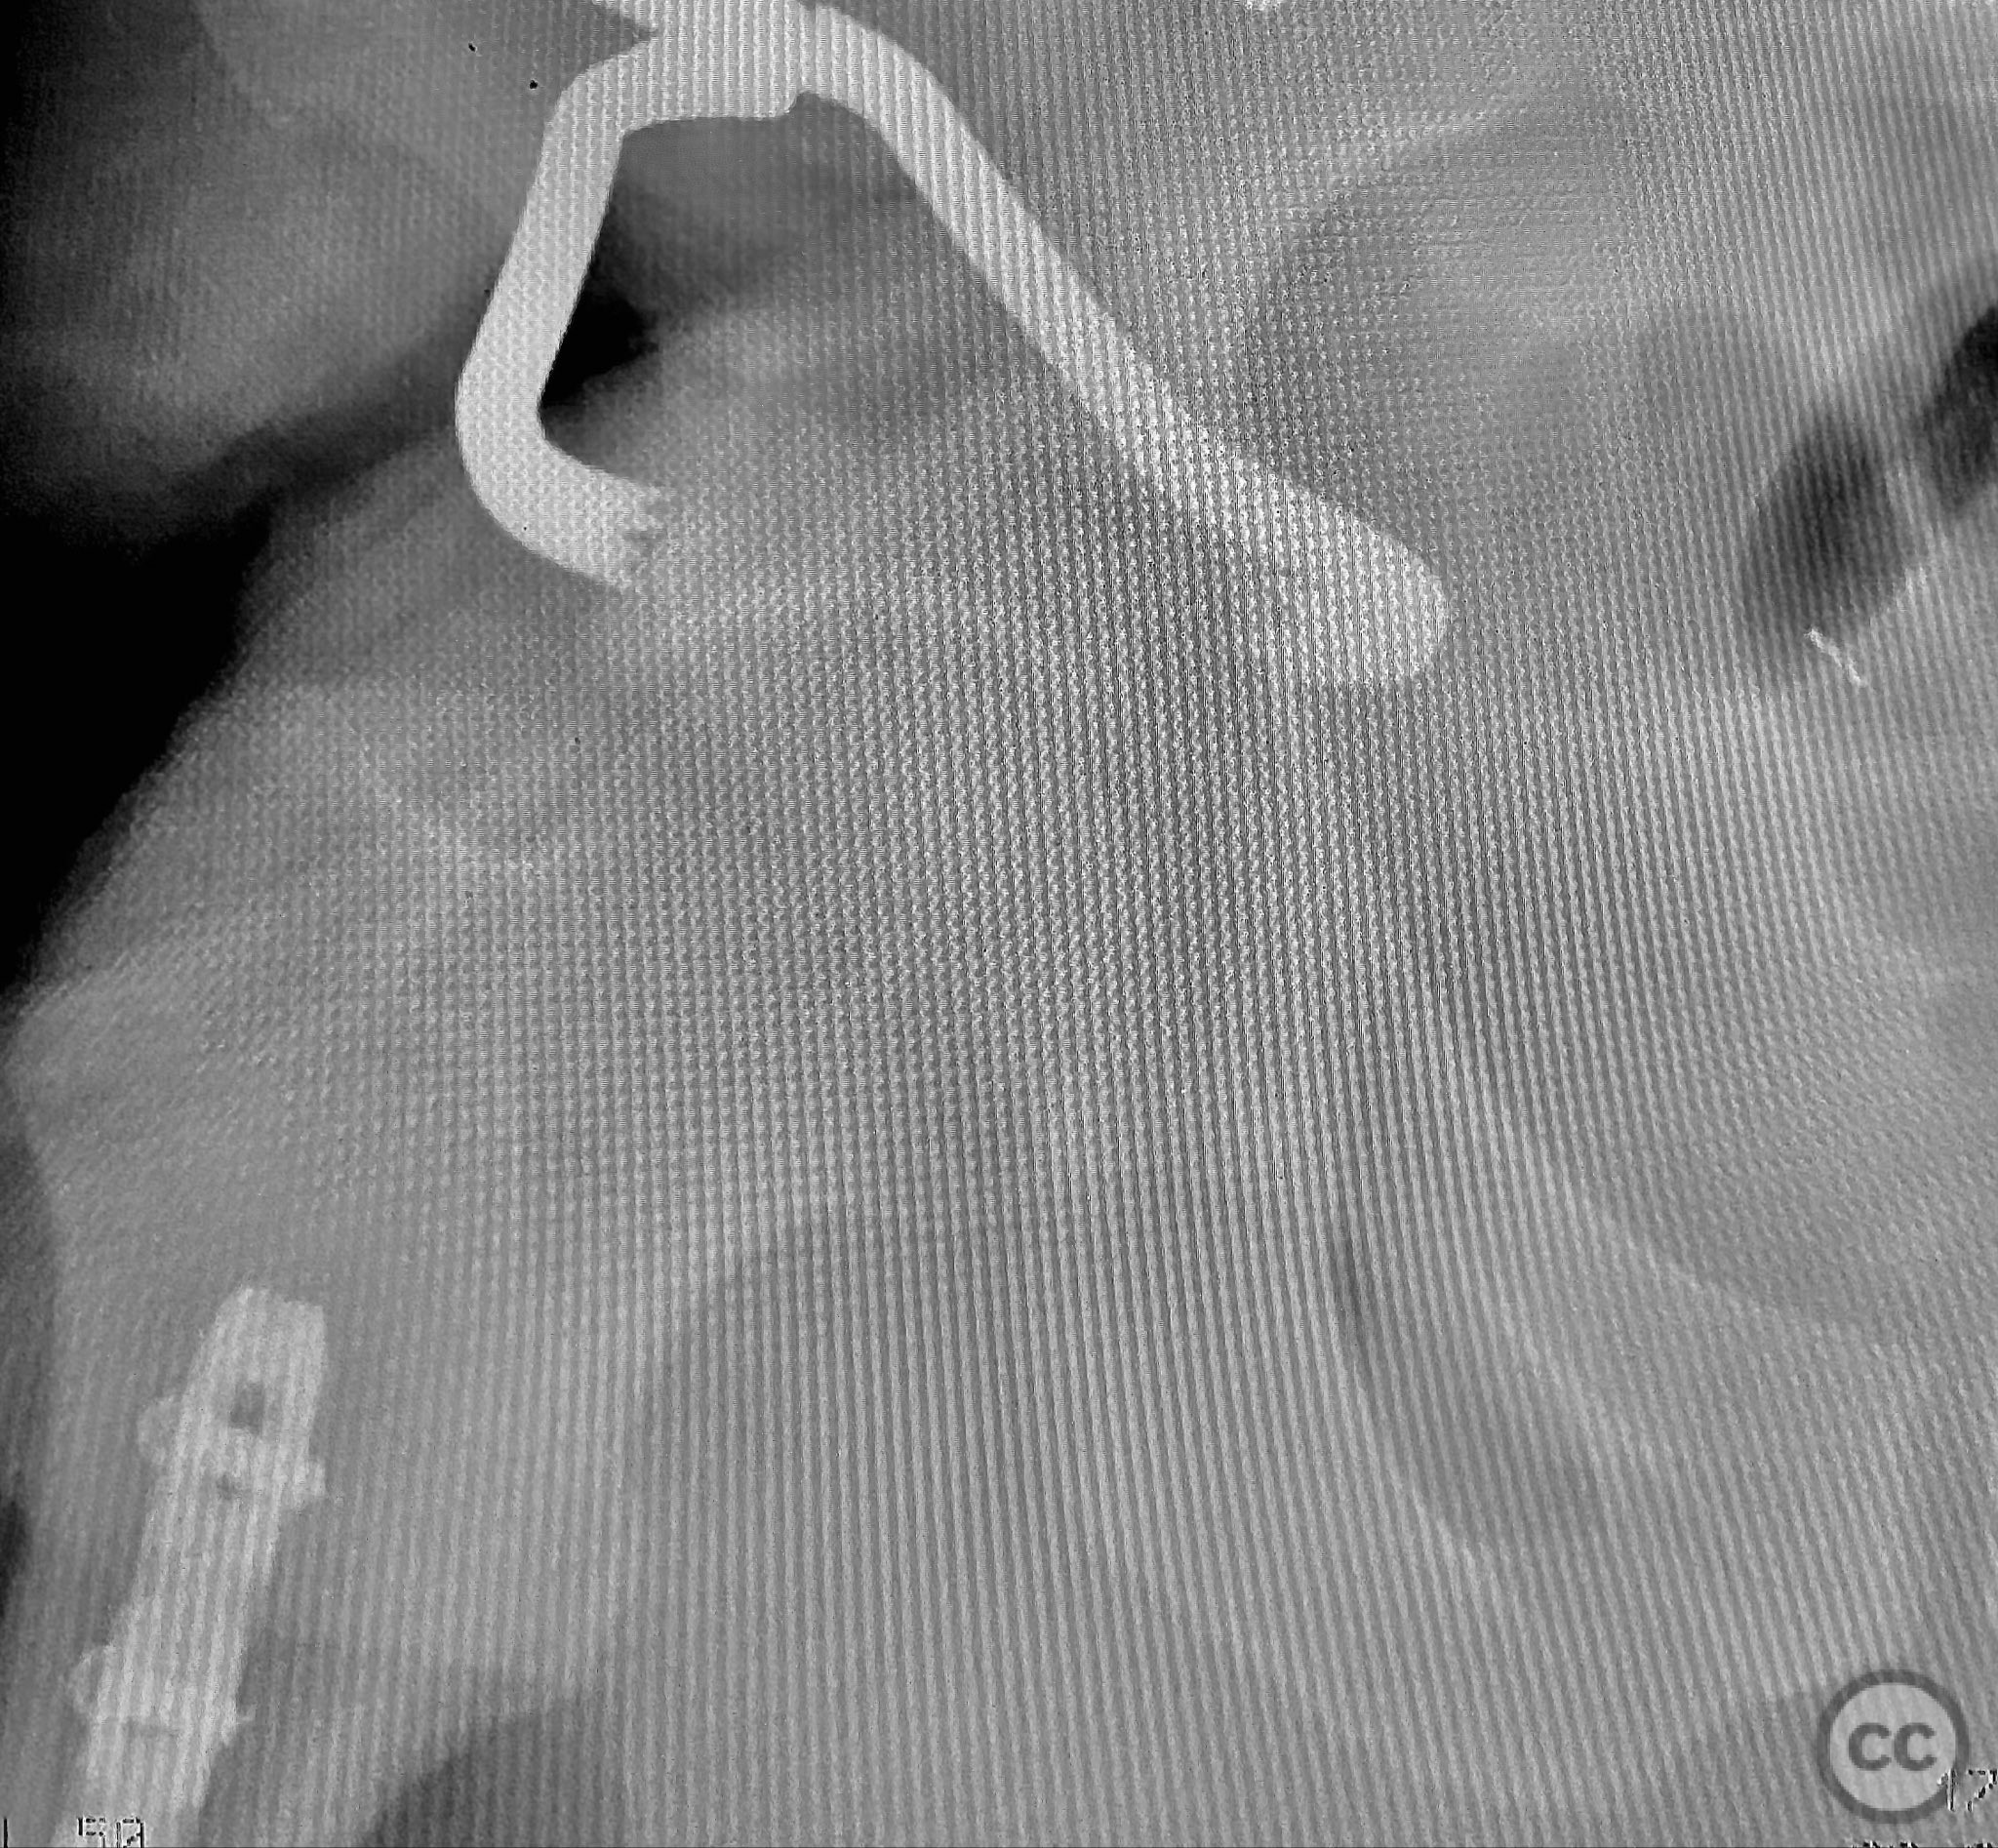

Clinical and radiological findings:  Adult male with a closed, comminuted left femoral shaft fracture and complex pelvic ring injury. Initial imaging demonstrated bilateral sacroiliac (SI) joint disruptions and a left-sided transtectal transverse acetabular fracture (Letournel-Judet: transverse type), with the fracture line exiting through the posterior wall region but without a discrete posterior wall fragment. The femoral head was displaced caudally, following the unstable distal acetabular segment, resulting in loss of congruency with the intact acetabular dome. There was also a symphyseal disruption. No associated abdominal, visceral, thoracic, cranial, or other injuries were present. Application of a circumferential pelvic binder resulted in visible changes in pelvic alignment on imaging. AO/OTA Classification: - Pelvic ring: 61-C1.3 (bilateral SI joint disruption, complete instability) - Acetabulum: 62-B1 (transverse fracture) - Femur: 32-C3 (comminuted diaphyseal fracture)

Initial reduction of the posterior column was attempted using a Jungbluth clamp; however, intraoperative fluoroscopy revealed suboptimal reduction despite satisfactory direct visualization. A perpendicular reduction clamp was then applied, resulting in improved alignment as confirmed by fluoroscopy. The transverse acetabular fracture was stabilized with two 4.5 mm cortical screws placed across the fracture line, followed by application of posterior column plates for additional stability. The symphyseal disruption was managed non-operatively without direct stabilization.